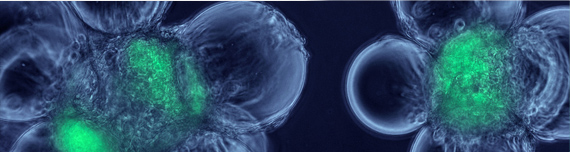

Many generic drug companies have invested in biologics to participate in the biosimilar opportunity. As a CRO with experience in conducting Innovator biologic studies and ten biosimilar studies, we are called upon to conduct biosimilar clinical studies.